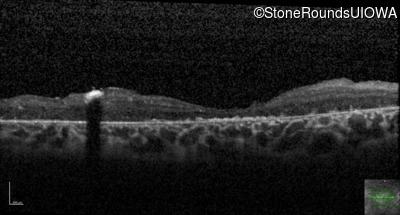

Optical Coherence Tomography - Right - 20/400 sc

Exemplar / OCT Stack